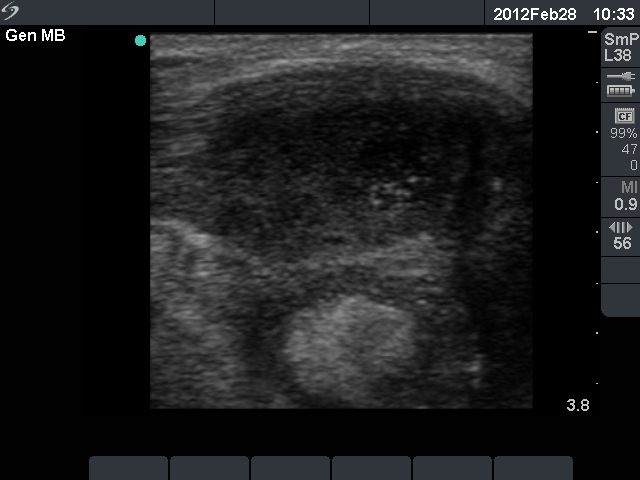

Third row: 3 days after the fourth session of ethanol treatment - the cyst became more enlarged and painful. The body temperature rose to 38.2 C, the erythrocyte sedimentation rate was 50 mm/H.

Ultrasonography: the size of the nodule was 30x25x34 mm, and another hyperechogenic lesion was found dorsal to the treated lesion.

Steroid administration resulted in a prompt amelioration of the clinical symptoms. The steroid was given for 6 weeks in a decreasing dose.